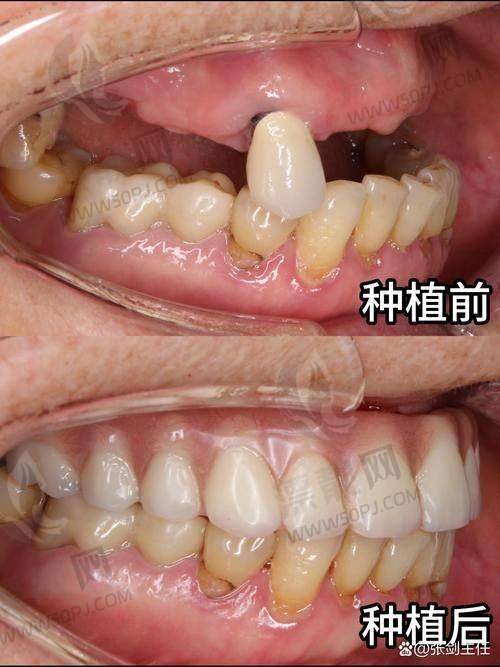

?种植牙:国内外有名品牌全覆盖,医生种植经验多,缺牙烦恼解决快准稳。